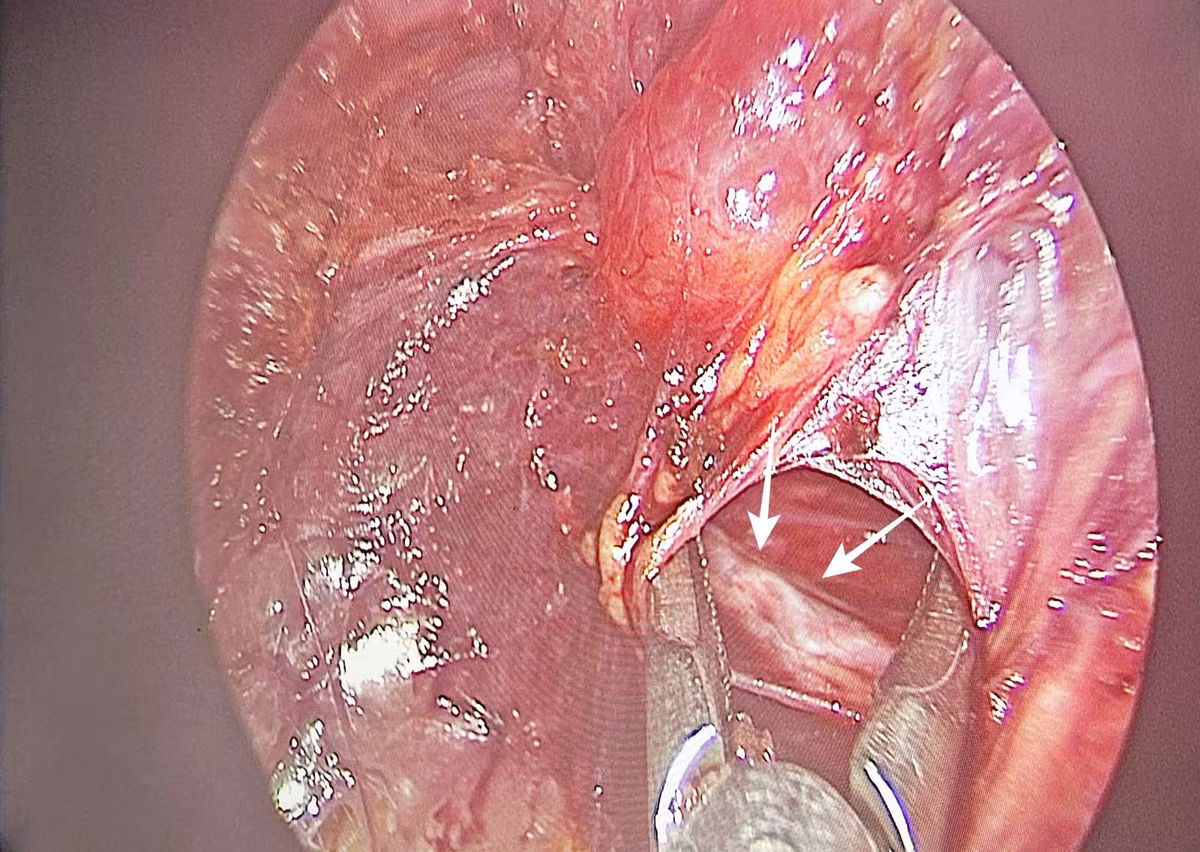

Qua 3 đường rạch nhỏ ở môi trước trong khoang miệng, phẫu thuật viên thực hiện bóc tách lớp dưới cơ bám da cổ để đưa dụng cụ nội soi vào tuyến giáp theo đường giữa, kíp mổ khéo léo phẫu tích cắt thùy trái chứa khối ung thư và eo tuyến giáp, nạo vét hạch cổ, bảo tồn dây kinh thần kinh thanh quản quặt ngược và tuyến cận giáp.

Hình ảnh phẫu tích cắt thùy trái chứa khối ung thư và eo tuyến giáp, nạo vét hạch cổ, bảo tồn dây kinh thần kinh quặt ngược - Ảnh BVCC